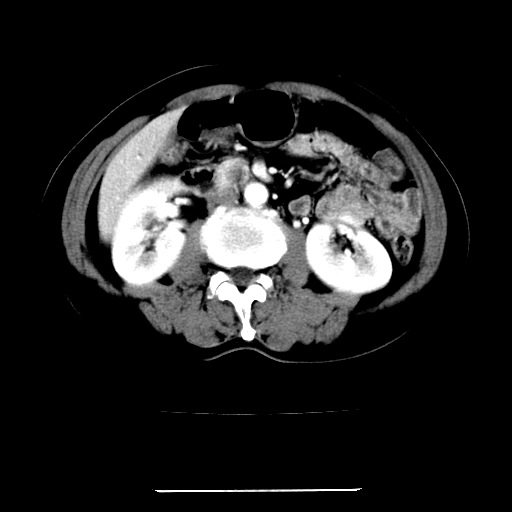

标题: CT22301:女,67岁,上腹部疼痛一周伴皮肤黄染,无发热。 [打印本页]

女,67岁,上腹部疼痛一周伴皮肤黄染,无发热。

左叶肝内胆管结石,并远端肝内胆管扩张。

考虑:肝内胆管结石继发肝内胆管扩张,右肾旋转不良。

肝内外胆管结石并肝内胆管扩张。

肝内外胆管扩张,左叶胆管内结石

1、肝门高密度影下层面和胰头层面可见轻度胆管扩张,而静脉和延迟期均未见扫描完胰头,不能完全排除胰头占位。2、肝门部高密度影,考虑钙化或结石。

考虑肝门胆管癌伴门脉左支受侵包埋,建议mrcp进一步检查。